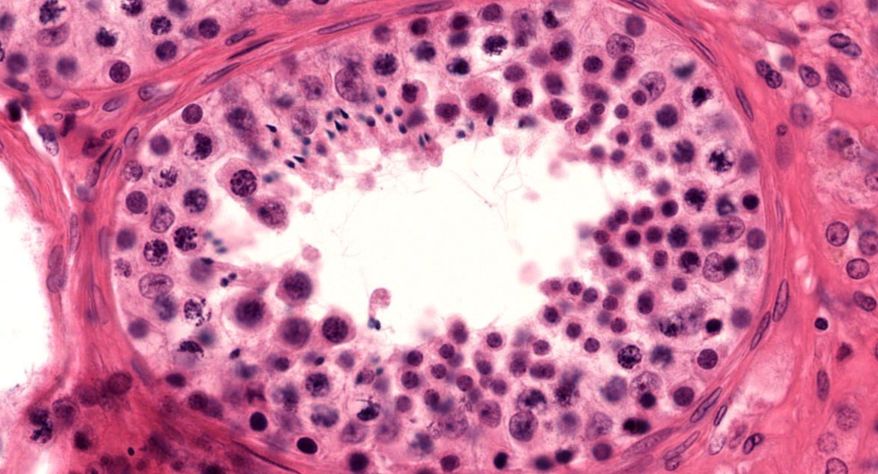

低倍镜:睾丸表面为鞘膜覆盖,其上皮为单层扁平上皮,鞘膜下是一层较厚的致密结缔组织,叫做白膜。白膜在睾丸后缘增厚,形成睾丸纵隔,其内可见不规则的腔隙,即睾丸网。睾丸内可见很多上皮性管道的切面,即生精小管的切面,呈圆形或椭圆形,管壁较厚,由生精上皮及其明显的基膜等组成。高倍镜:着重观察生精小管和其之间的睾丸间质。生精小管主要由生精上皮构成。生精上皮由生精细胞和支持细胞组成。生精细胞是一组细胞,依次自基膜向管腔面排列。

1.睾丸全景图

5.生精小管

6.生精上皮

8.精原细胞

9.初级精母细胞

10.精子细胞

11.精子